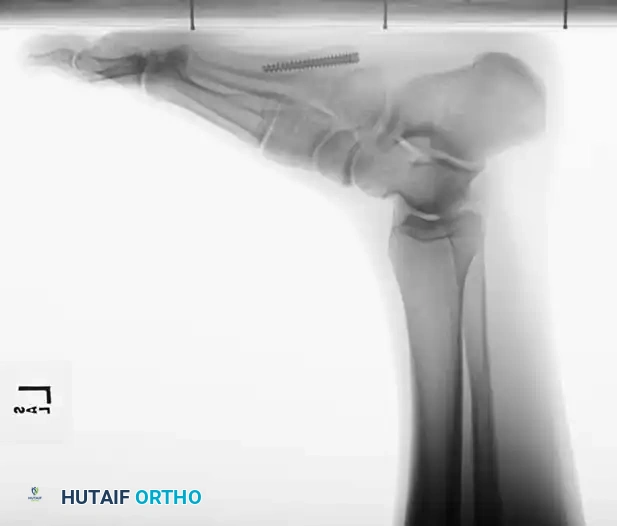

Fig. 86-44, cont’d D-F, After screw fi xation.

Fig. 86-44 D-F. Postoperative radiographs following precise open reduction and internal screw fixation, restoring the articular surface.